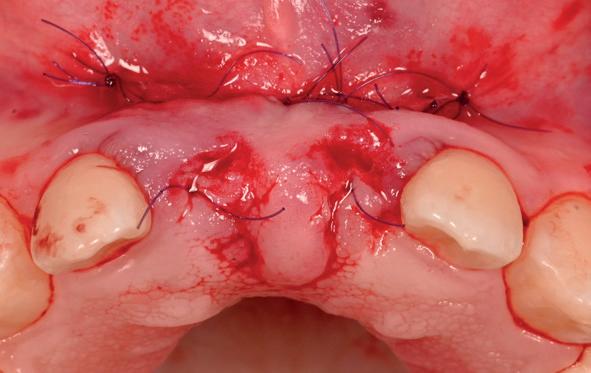

• Aanvulling zachte weefsels met de VISTA techniek en een vrij gingivatransplantaat uit het palatum links en direct dragen van de essix retainer

Na 4 weken intra-orale scan voor de etsbrug en kleurbepaling bij de technicus

pincisies met hechtingen naar het buccale en coronale deel getrokken en aldaar ingehecht. Met twee incisies werd ook de emergence profile gecreëerd (afbeelding 6-13). Voor een goede genezing van het

13. Occlusaal beeld verdikking van de zachte weefsels

14. Direct postoperatief plaatsen

van de essix met 2 dummy tanden